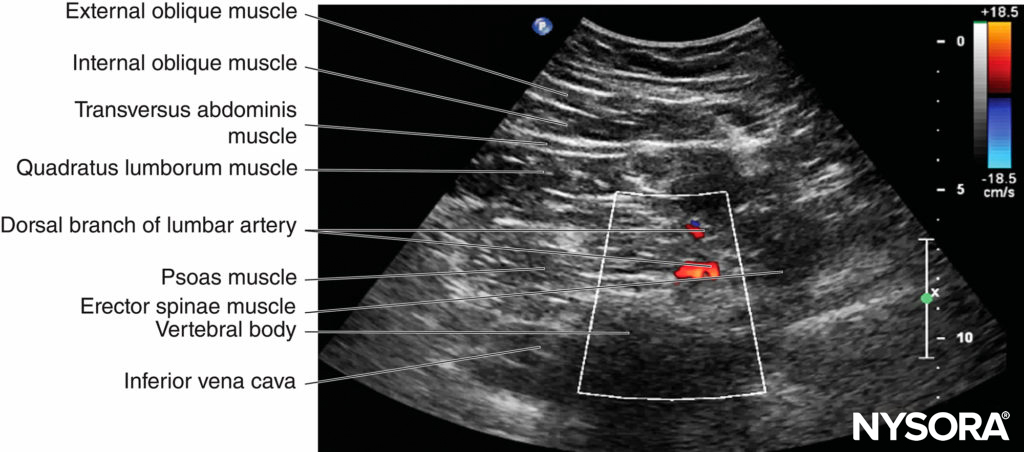

FIGURE 7. Color Doppler US images of the lumbar paravertebral region in the (A) transverse and (B) sagittal scan planes. Note the dorsal branch of the lumbar artery on the posterior aspect of the psoas muscle in both the transverse and sagittal sonograms and the spinal artery in the transverse sonogram. PMSS, paramedian sagittal scan; PMTOS, paramedian transverse oblique scan.

The lumbar paravertebral region is highly vascular and contains the ascending lumbar veins and lumbar arteries, which can be visualized using color and power Doppler US (see Figures 7 and 19). There is also a rich network of blood vessels (arteries and veins) within the substance of the psoas major muscle including the psoas compartment. The dorsal branch of the lumbar artery is also closely related to the transverse processes and the posterior aspect of the psoas muscle (see Figure 7b), where the lumbar plexus is located.

Therefore, this blood vessel may be at risk of needlerelated injury during LPB because it is directly in the path of the advancing needle (see Figure 7). Considering the vascularity of the lumbar paravertebral region, it is not surprising that inadvertent intravascular injection of local anesthetic and psoas hematoma have been described after LPB. It is for the same reason that one must exercise caution when considering an LPB in patients with mild to moderate coagulopathy or in patients receiving thromboprophylaxis; based on our current understanding, such conditions may be considered a relative contraindication for LPB. That said, there are reports of the safe use of LPB (both the single-injection and continuous techniques) before the initiation of postoperative thromboprophylaxis and the removal of catheters in patients receiving thromboprophylaxis and/or aspirin with an international normalized ratio (INR) of equal to or greater than 1.5. One must exercise caution in interpreting such results, however, because the site at which an LPB is performed is noncompressible, and there are previous reports of retroperitoneal hematoma complicating LPB. Moreover, there are currently very few evidence-based indications for LPB.